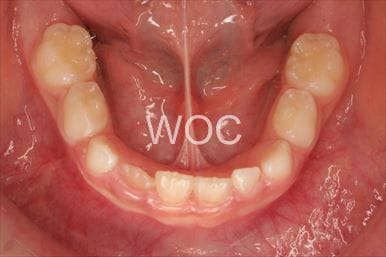

八重歯・叢生上のみ舌側矯正、下はエッジワイズ装置

上は舌側矯正を希望。ガタガタ(叢生)が強い。上顎右側中切歯・側切歯が歯科治療で連結してあったがそれを除去してから治療開始しました。

- 年齢:23歳女性

- 主訴:上下前歯のガタガタが気になる

- 基本矯正料金:103万円

- 治療期間:2年2ヶ月

- 非抜歯